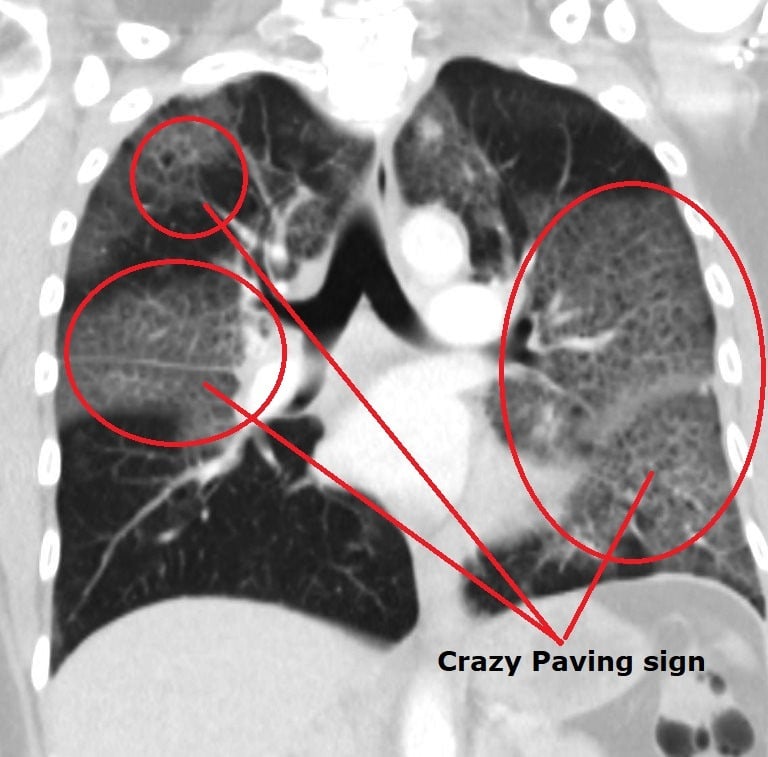

Bilateral Periferik Buzlu Cam Görünümü (GGO): Alveoler boşlukların proteinöz eksüda, hiyalin membranlar ve inflamatuar hücrelerle kısmen dolması. LR+ 4.8 Skor: +4 Puan

Kaldırım Taşı (Crazy-Paving) Patern: Buzlu cam zemininde interlobüler septal kalınlaşma; tablonun ilerlediğinin (akut faz) kanıtı. LR+ 3.5 Skor: +3 Puan